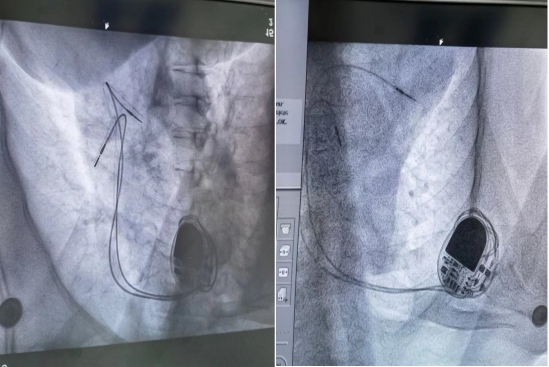

起搏器安装术后造影图

梁远红主任抵达我院后,立即与张先生及家属沟通交流病情,结合病史及辅助检查制定了手术方案,与我院心血管内科团队为其施行心脏起搏器植入术,历时1小时8分钟顺利完成手术,成功植入了心脏起搏器。起搏器感知和功能良好,术后张先生头晕、胸闷、黑曚症状完全消失,心率稳定在70次/分以上并康复出院。

术后心电图,可看到明显的起搏钉